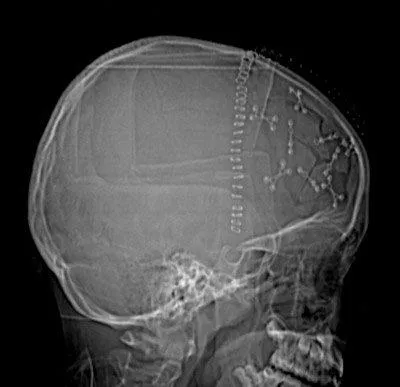

His daughter was rushed into emergency surgery for surgeons to attempt to put her little skull back together with metal plates and pins. Her skull was shattered into 31 tiny pieces.